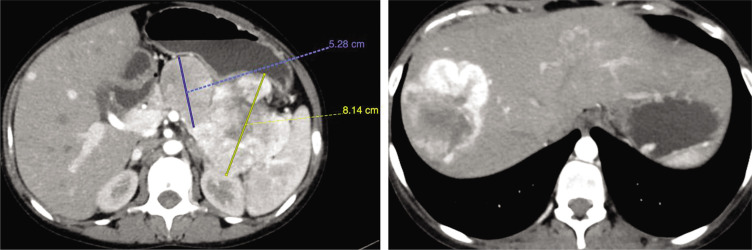

A 25-year-old woman presented with metastatic pancreatic neuroendocrine tumor with carcinoid syndrome. She was refractory to octreotide and did not respond well to chemotherapy. Although surgical debulking remains the primary approach for managing these tumours, it entails inherent risks, including potentially exacerbating carcinoid syndrome. We strategically delivered the one Peptide Receptor Radionuclide Therapy cycle before tumor debulking, a decision that yielded a remarkable response, stabilizing her condition.